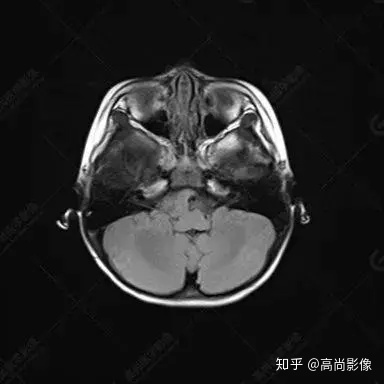

右側(cè)顳葉腫瘤切除術(shù)后(具體不詳):右側(cè)顳部骨質(zhì)不連續(xù)呈術(shù)后改變,右側(cè)顳葉術(shù)區(qū)見片狀長T1長T2信號影,F(xiàn)LAIR呈低信號;術(shù)區(qū)后方右側(cè)顳枕葉見一巨大占位性病變影,邊界欠清,大小約6.2×5.8×4.3cm(前后×左右×上下),信號不均勻,T1WI呈等稍低信號間雜少許高信號,T2WI呈高稍低混雜信號,DWI示部分病灶彌散受限,相應(yīng)ADC圖減低,磁敏感序列見部分呈極低信號,增強(qiáng)掃描可見明顯不均勻強(qiáng)化,鄰近硬腦膜及小腦幕增厚并明顯強(qiáng)化;另延髓右前方及右側(cè)橋小腦角區(qū)見一不規(guī)則形異常信號影,大小約3.2×1.3×3.7cm(左右×前后×上下),呈長T1稍長T2信號,F(xiàn)LAIR呈等信號,DWI未見受限,增強(qiáng)后明顯均勻強(qiáng)化,鄰近腦膜明顯強(qiáng)化。鄰近腦實質(zhì)及右側(cè)顳角明顯受壓;左側(cè)大腦半球未見局灶性信號異常,中線結(jié)構(gòu)稍左移。

右側(cè)顳葉腫瘤切除術(shù)后:現(xiàn)術(shù)區(qū)后方右側(cè)顳枕葉及延髓右前方占位,右側(cè)顳枕部硬腦膜及小腦幕明顯強(qiáng)化,結(jié)合既往影像資料,考慮為胚胎源性惡性腫瘤,如非典型畸胎樣/橫紋肌樣瘤(AT/RT)或原始神經(jīng)外胚層腫瘤(PNET)。

術(shù)后隨訪病理結(jié)果:非典型畸胎樣/橫紋肌樣瘤。